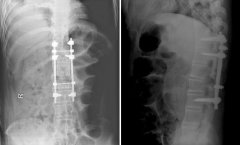

QZ16030094 姓名:陈先生 性别:男 年龄:32岁

- 病情

AS ①晚期 ②重度 病史:5年+

- 治疗

治疗后骶髂关节疼痛消失,腰椎前屈、背伸侧弯活动自如,膝关节无压痛感,复查血沉、C反应蛋白、等各项检查均已达到临床康复的标准。